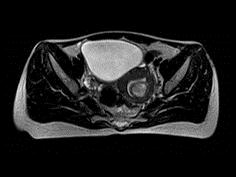

问题 35岁女性患者,曾行剖宫产手术,有痛经史5年,近来加重,行MRI检查,如图所示,请选择正确的答案 ( )

选项 A、卵巢表皮样囊肿 B、卵巢粘液性囊肿 C、子宫颈癌 D、卵巢囊肿 E、子宫内膜异位症

答案 E